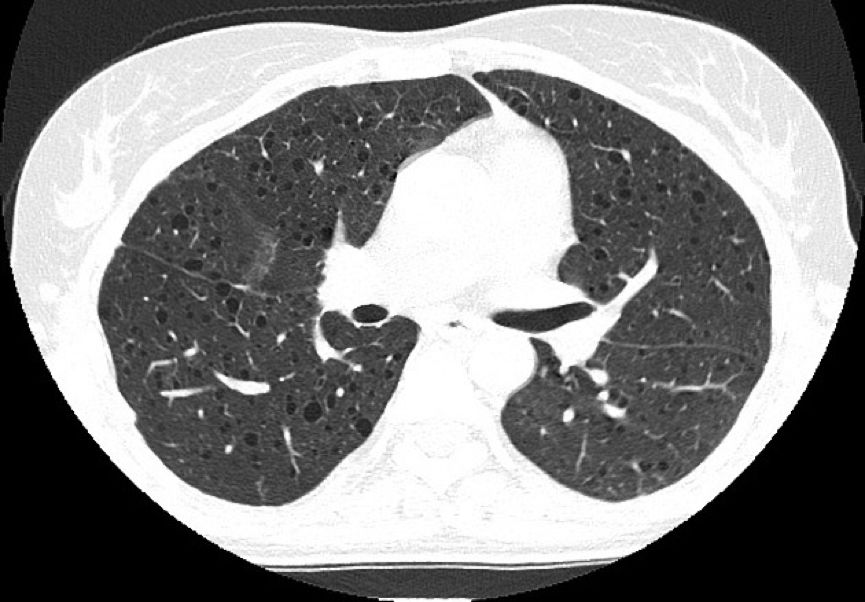

病例2:患者女性,36岁,胸痛一周加重伴呼吸困难。

常规CT表现为两肺密度减低,体积增大,呈肺气肿样改变。HRCT对本病的早期诊断及病情发展的监测有重要意义,其特征性改变为两肺广泛弥漫性分布的薄壁小囊状病变,两侧对称,无上中下肺野的区别,也无中央性与周围性的分布差异。囊腔直径为2~30 mm,大多数直径小于10 mm,囊壁厚度多小于2 mm。